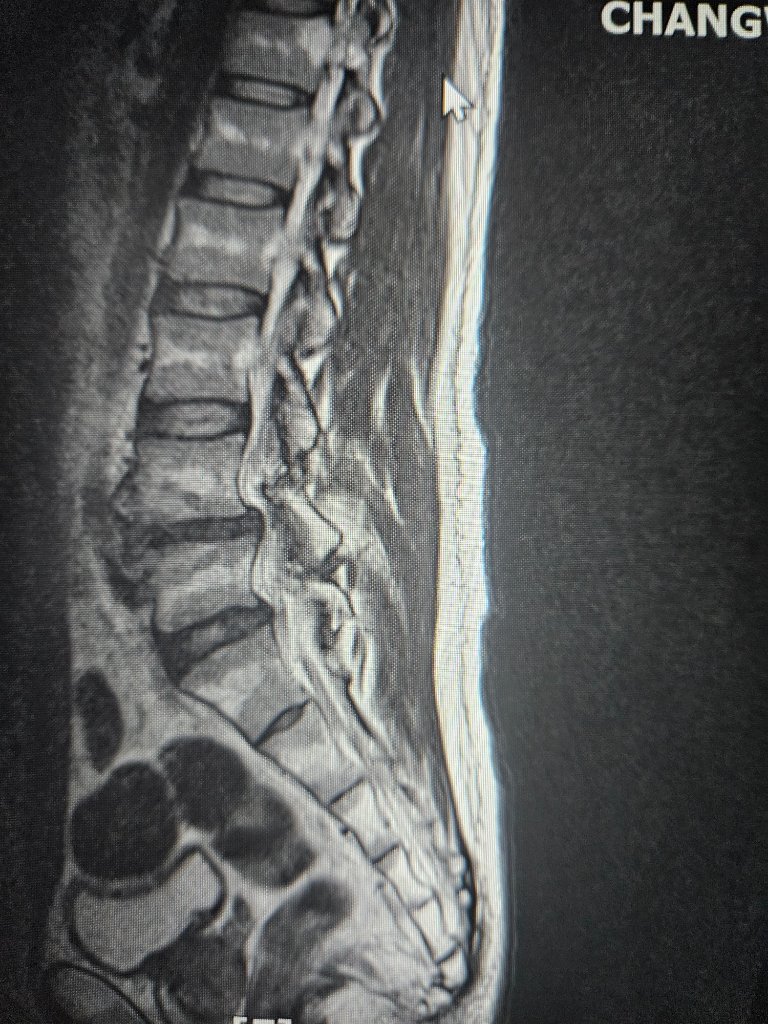

수술해야될 정돈지 사진보시고 확인좀 해주세요

척추분리증과 전방전위증등으로 통증이 너무심한데

허리부터 다리까지 통증이 있고 종아리까지 전기가 찌릿한 증상 누워있을때는 그나마 참을만 한데 그외 다른자세를 하면 통증이 심해집니다

걷는것도 10분이상하면 허리 부터 허벅지 까지 통증이 심하게 생깁니다

척추분리증은 30년 정도 되었고 다른건 10년이 넘은거 같습니다

약이나 물리치료도 오래 했지만 지금은 효과도 없고 시술또한 별다른 효과가 없어서 통증으로 인한 예민함과 잠잘때 힘이들어 정신과약을 복용중입니다

사진과함께 증상을 종합해봤을때 수술이 필요한지 아니면 보존치료가 더 나은지 궁금 합니다

보내주신 사진만으로는 정확한 진단을 내리기 어렵습니다. 정확한 진단을 위해서는 전문의의 진찰과 검사가 필요합니다. 하지만 사진과 증상을 종합해보면 수술을 고려해볼 수 있는 수준으로 보입니다.

척추분리증과 전방전위증은 척추뼈가 정상적인 위치에서 벗어나 발생하는 질환입니다. 이 질환은 허리와 다리에 통증, 저림, 감각 이상 등의 증상을 유발할 수 있습니다.

보존치료는 약물치료, 물리치료, 침술, 도수치료 등이 있습니다. 하지만 보존치료로 증상이 개선되지 않거나 다음과 같은 경우 수술을 고려해야 합니다.

• 심한 통증으로 인해 일상생활에 지장이 있는 경우

• 보존치료를 6개월 이상 시도했음에도 불구하고 증상이 개선되지 않는 경우

• 신경 손상으로 인해 근력 저하, 대소변 장애 등이 발생한 경우

수술 방법은 여러 가지가 있으며, 환자의 상태에 따라 적절한 방법을 선택합니다. 일반적으로 척추뼈를 고정하는 척추유합술이 시행됩니다.

수술은 통증 완화에 효과적이지만, 합병증 위험도 있습니다. 따라서 수술을 결정하기 전에 전문의와 충분히 상의하여 수술의 장단점을 신중하게 고려해야 합니다.

현재의 증상을 고려했을 때, 전문의와 상담하여 수술이 필요한지, 아니면 보존치료를 지속할지 결정하는 것이 좋습니다.